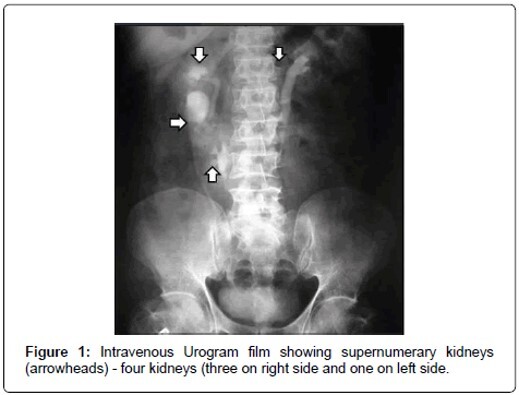

7

Q

What pathology is seen here?

A

Supernumerary Kidney